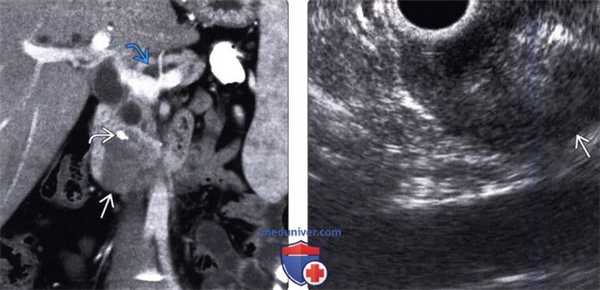

(Левый) При КТ с контрастным усилением на корональной томограмме в головке поджелудочной железы определяется крупное гетерогенное объемное образование пониженной плотности; наблюдается внутриопухолевый кальциноз, что указывает на злокачественную природу опухоли. Обратите внимание на расширение панкреатического протока вследствие наличия объемного образования головки поджелудочной железы.

(Правый) При эндоскопическом УЗИ на соответствующем УЗ срезе визуализируется четко отграниченное гипоэхогенное солидное объемное образование поджелудочной железы.